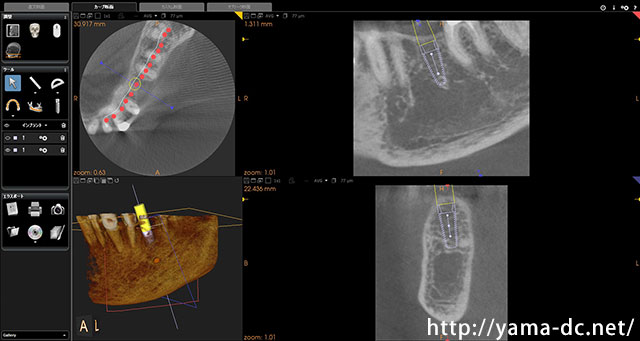

CTを用いることで従来の平面的なレントゲン画像では難しいとされる顎の骨を立体的に確認することができます。

きちんと神経の位置や骨の状態を確認した上で治療計画を立て、患者様に安心・安全なインプラント治療をご提供しています。